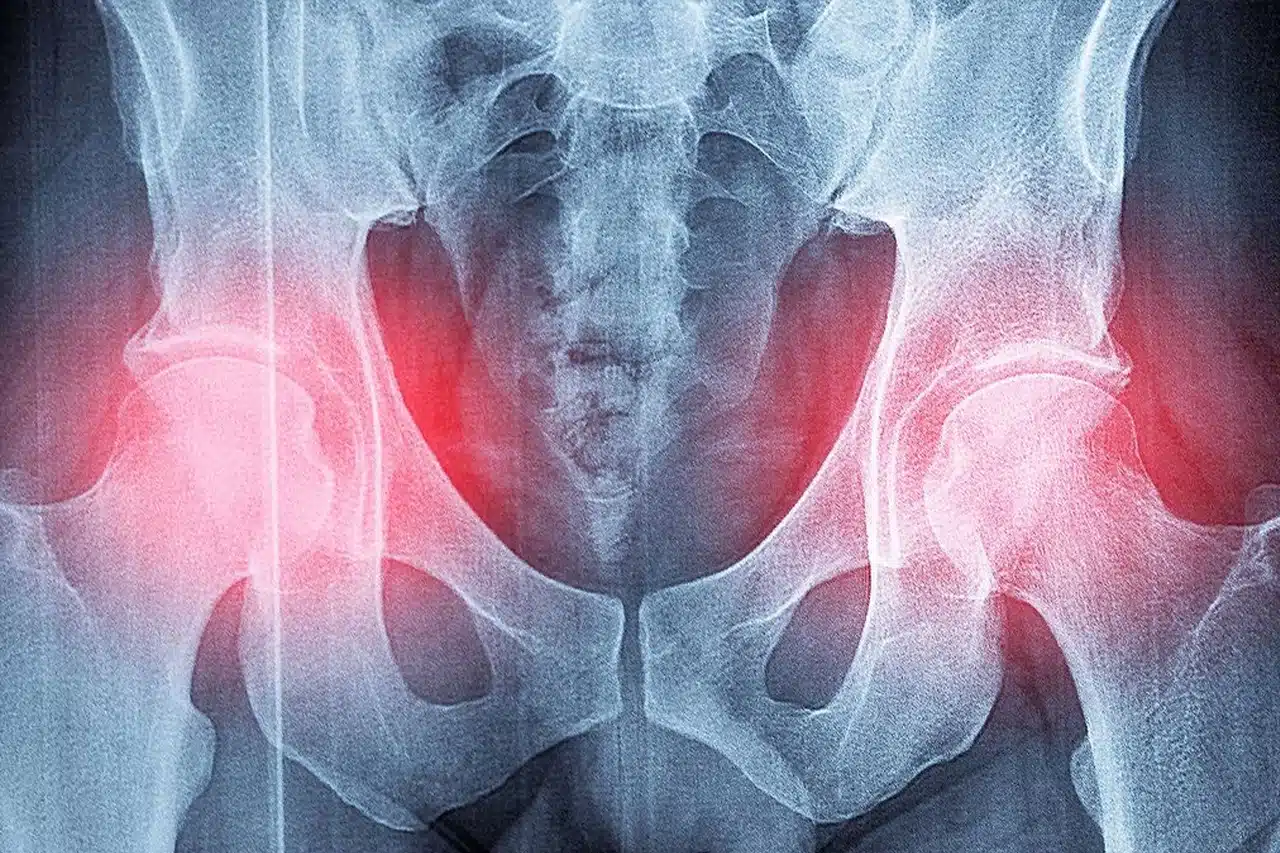

Fragility fractures increase sharply with age and, since osteoporosis often causes no symptoms at the beginning, you must remain vigilant starting in your fifties. Among people over 80, the hip is the most frequent fracture and the one that leads to the heaviest functional and vital consequences. For this reason, it is essential to ensure fall prevention, such as in the bathroom, for example.

Risk of long, disabling complications

After a hip fracture, there is a one in four chance of all-cause mortality within a year. A significant proportion of people suffering from a hip fracture never regains their previous level of autonomy.